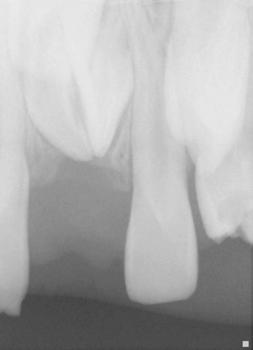

The following procedures were accomplished under general anesthesia on an outpatient basis — full mouth dental radiographs and a comprehensive oral exam. A complex odontoma was found to be the etiology of the noneruption of the maxillary right permanent central incisor (Figure 2). Since dental caries also was diagnosed, a full-mouth prophylaxis was completed. Dental caries was controlled, and teeth were restored. A 5 mm incision was made on the gingiva over the impacted maxillary right permanent central incisor, and two tooth-like structures were extracted from the right maxillary incisor area. A postoperative periapical radiograph was taken to confirm complete odontoma removal (Figure 3). Three interrupted sutures using 3-O chromic gut were placed.

Figures 2 and 3: 2. Periapical radiograph of involved area taken in the operatory during initial dental rehabilitation under general anesthesia (left). 3. Periapical radiograph of involved area taken in the operatory during initial dental rehabilitation under general anesthesia immediately after odontoma removal (right)